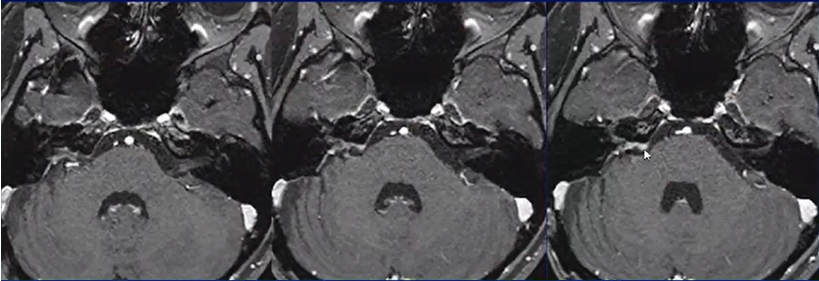

听神经瘤可引起内听道扩大, 突向小脑桥脑角部, 充填于小脑桥脑角内, 呈特征性的“冰激凌圆锥”征。甜筒冰激凌征为头颅MRI上,桥小脑角池占位的一端呈锥形、伸入同侧扩大的内听道内,一端膨大,位于桥小脑角池内,肿瘤形似甜筒冰淇淋。

典型听神经瘤MRI影像呈冰淇淋甜筒征